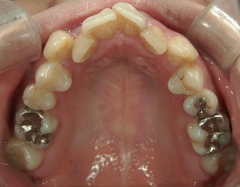

矯正歯科 治療前矯正歯科 治療前

矯正歯科 治療前 上下左右4番 計4本を抜歯して叢生を改善しました。

矯正_灰色.pngno.31_1962_治療前_上.JPG矯正_灰色.png

no.31_1962_治療前_右.JPGno.31_1962_治療前_正面.JPGno.31_1962_治療前_左.JPG